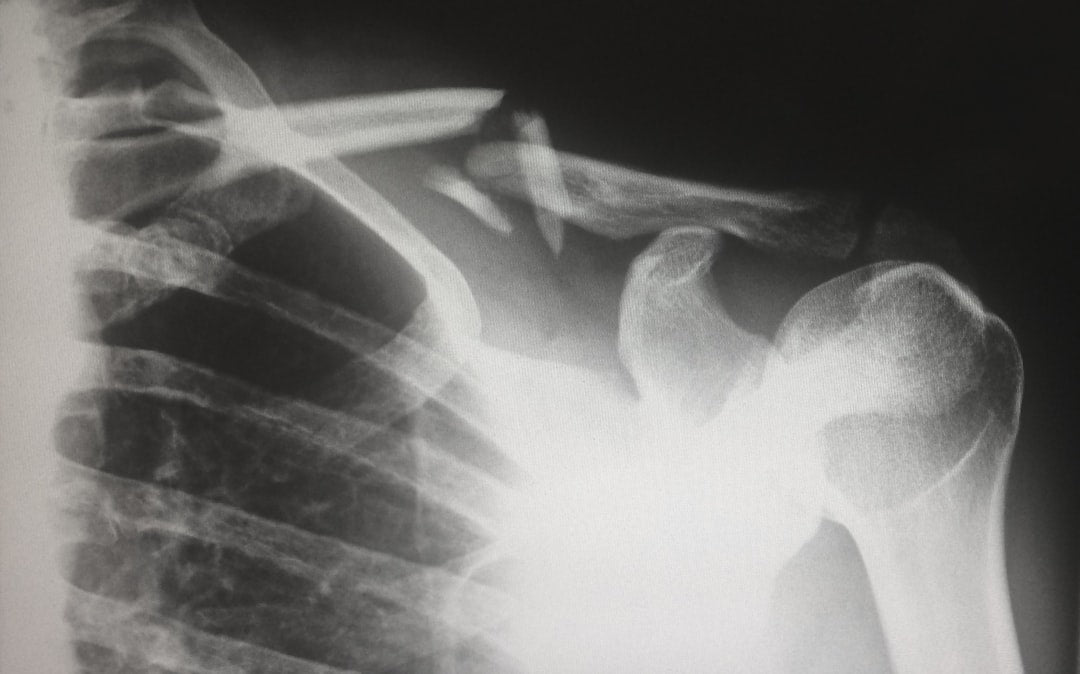

Frozen shoulder occurs when the capsule surrounding the shoulder joint becomes inflamed and stiff, leading to restricted movement and considerable pain. During menopause, hormonal fluctuations can increase the risk of developing this condition, particularly affecting women between ages 40 and 60.

Women experiencing frozen shoulder typically progress through three stages: freezing (increasing pain), frozen (stiffness), and thawing (gradual improvement). Medical experts have observed that symptoms often begin subtly, with many women initially dismissing the discomfort as normal aging or sleeping awkwardly.